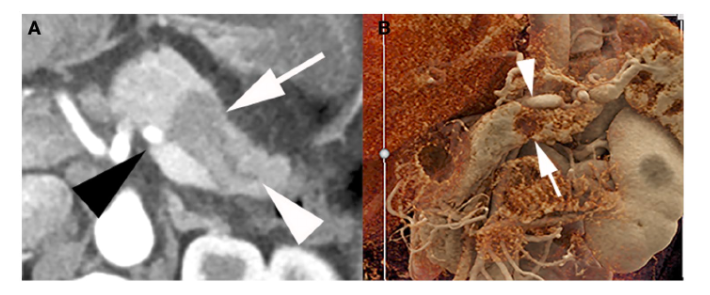

经“Society of Abdominal Radiology”和“American Pancreatic Association”认可的胰腺癌CT检查方案为:造影剂(>300mg /ml iodine)以3-5ml/秒的速度静注对比扫描获得胰腺实质期(40–50s)和门静脉期(65–70s)的CT检查。采用多平面重建方式将薄层扫描数据重建成0.75mm至3mm的轴向切片,三维(3D)重建以充分评估血管受累情况。电影渲染是一种最新的3D渲染技术,它可以提供接近真实病灶的细节,并有望提高肿瘤与血管关系的可视化成像技术(图1和图2)

图1:1例44岁女性可切除PDAC影像学资料